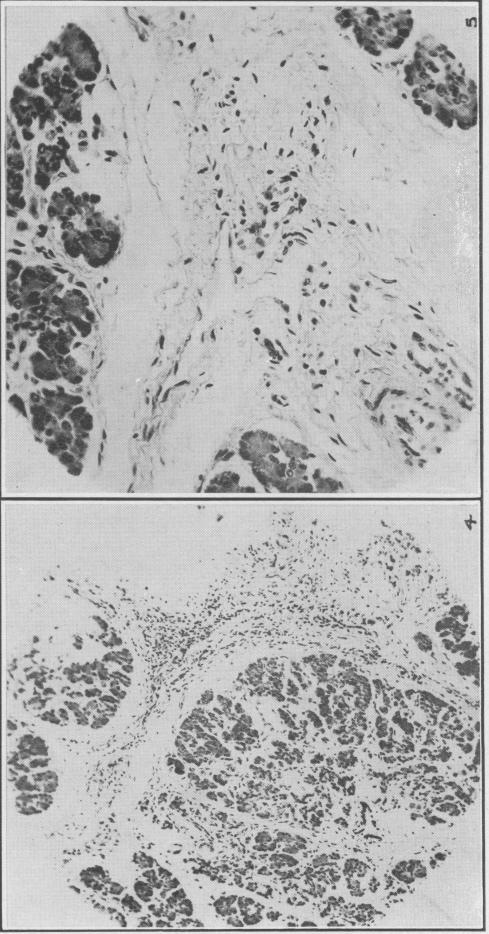

Structural and developmental abnormalities of the exocrine pancreas in cystic fibrosis.

J Pediatr Gastroenterol Nutr. 1984;3 Suppl 1:S55-66. doi: 10.1097/00005176-198400031-00011.

Endocrine pancreas in cystic fibrosis: an immunohistochemical study.

Hum Pathol. 1984 Mar;15(3):278-84. doi: 10.1016/s0046-8177(84)80191-4.